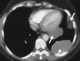

Benign metastasizing leiomyoma

Benign metastasizing leiomyoma is a rare condition characterized by the growth of uterine leiomyoma in the other regions especially the lungs. [Source: Wikipedia ]